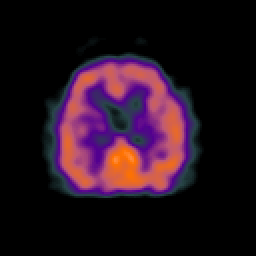

Normal aging, overlay -- Slice #36

[Home][Help][Clinical] Slice 36